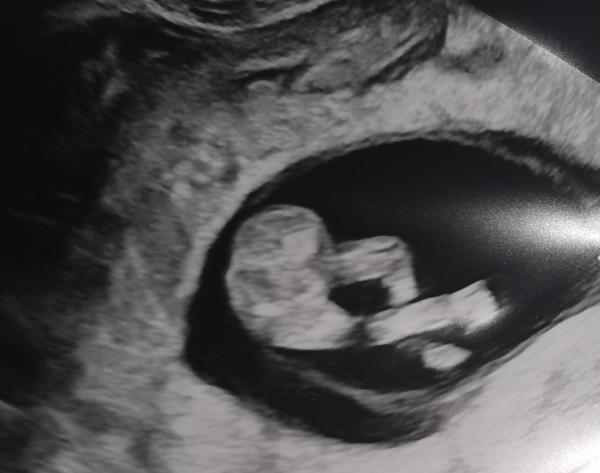

Unser Krümel ist soooo gewachsen.

Ist sogar schon 3 Tage "weiter"/"größer". Es war richtig schön zu sehen was alles dazu gekommen ist. Unser Krümel hatte auch scheinbar eine entspannte Zeit während dem Ultraschall: es sah aus als würde es auf einer Sonnenliege liegen. 😄 Arm hinter dem Kopf verschrenkt, die Beine dabei noch überkreuzt. Haben davon auch Bilder bekommen, und an den Füßchen kann man sogar schon die Zehen zählen 😍. Der Fuß wurde auch gemessen, hat schon 1cm Länge. Das Herzchen hat auch wieder kräftig geschlagen. Alles in allem also so, wie es sein soll. Einen Nub haben wir allerdings nicht gesehen, es gab auch keine Profil-Ansicht. Aber Details waren trotzdem deutlich zu erkennen, wie zB die Augen.

Den Ultraschall hat sie noch vaginal gemacht, meinte aber beim nächsten mal wird es dann über den Bauch. Bei ihr bin ich dann wieder in der 16. Ssw, also noch 4 Wochen hin. Da wir aber in zwei Wochen die frühe Feindiagnostik haben, ist die Wartezeit nicht ganz so lange. Ich hoffe, da bestätigt sich das unauffällige Ergebnis vom NIPT. 👍🏻